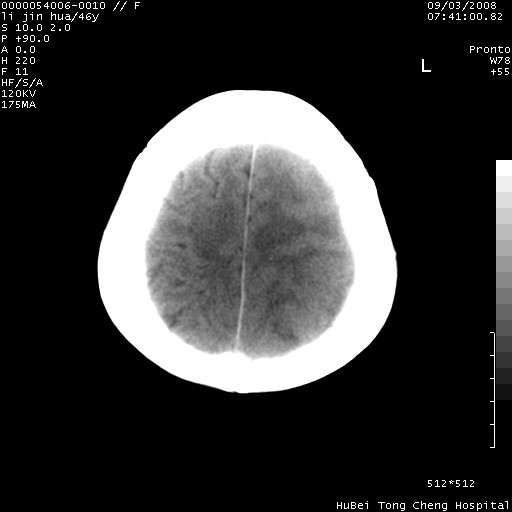

以下是引用panyishengct在2008-9-6 1:47:00的发言:[br]病史?[br]左侧枕/顶叶见一等/低混杂密度占位,壁完整,厚薄较均匀,其前方似有一类似小病灶,周围有水肿带,请结合病史考虑,脓肿可能,不排外转移瘤或胶质瘤,建议增强扫描。